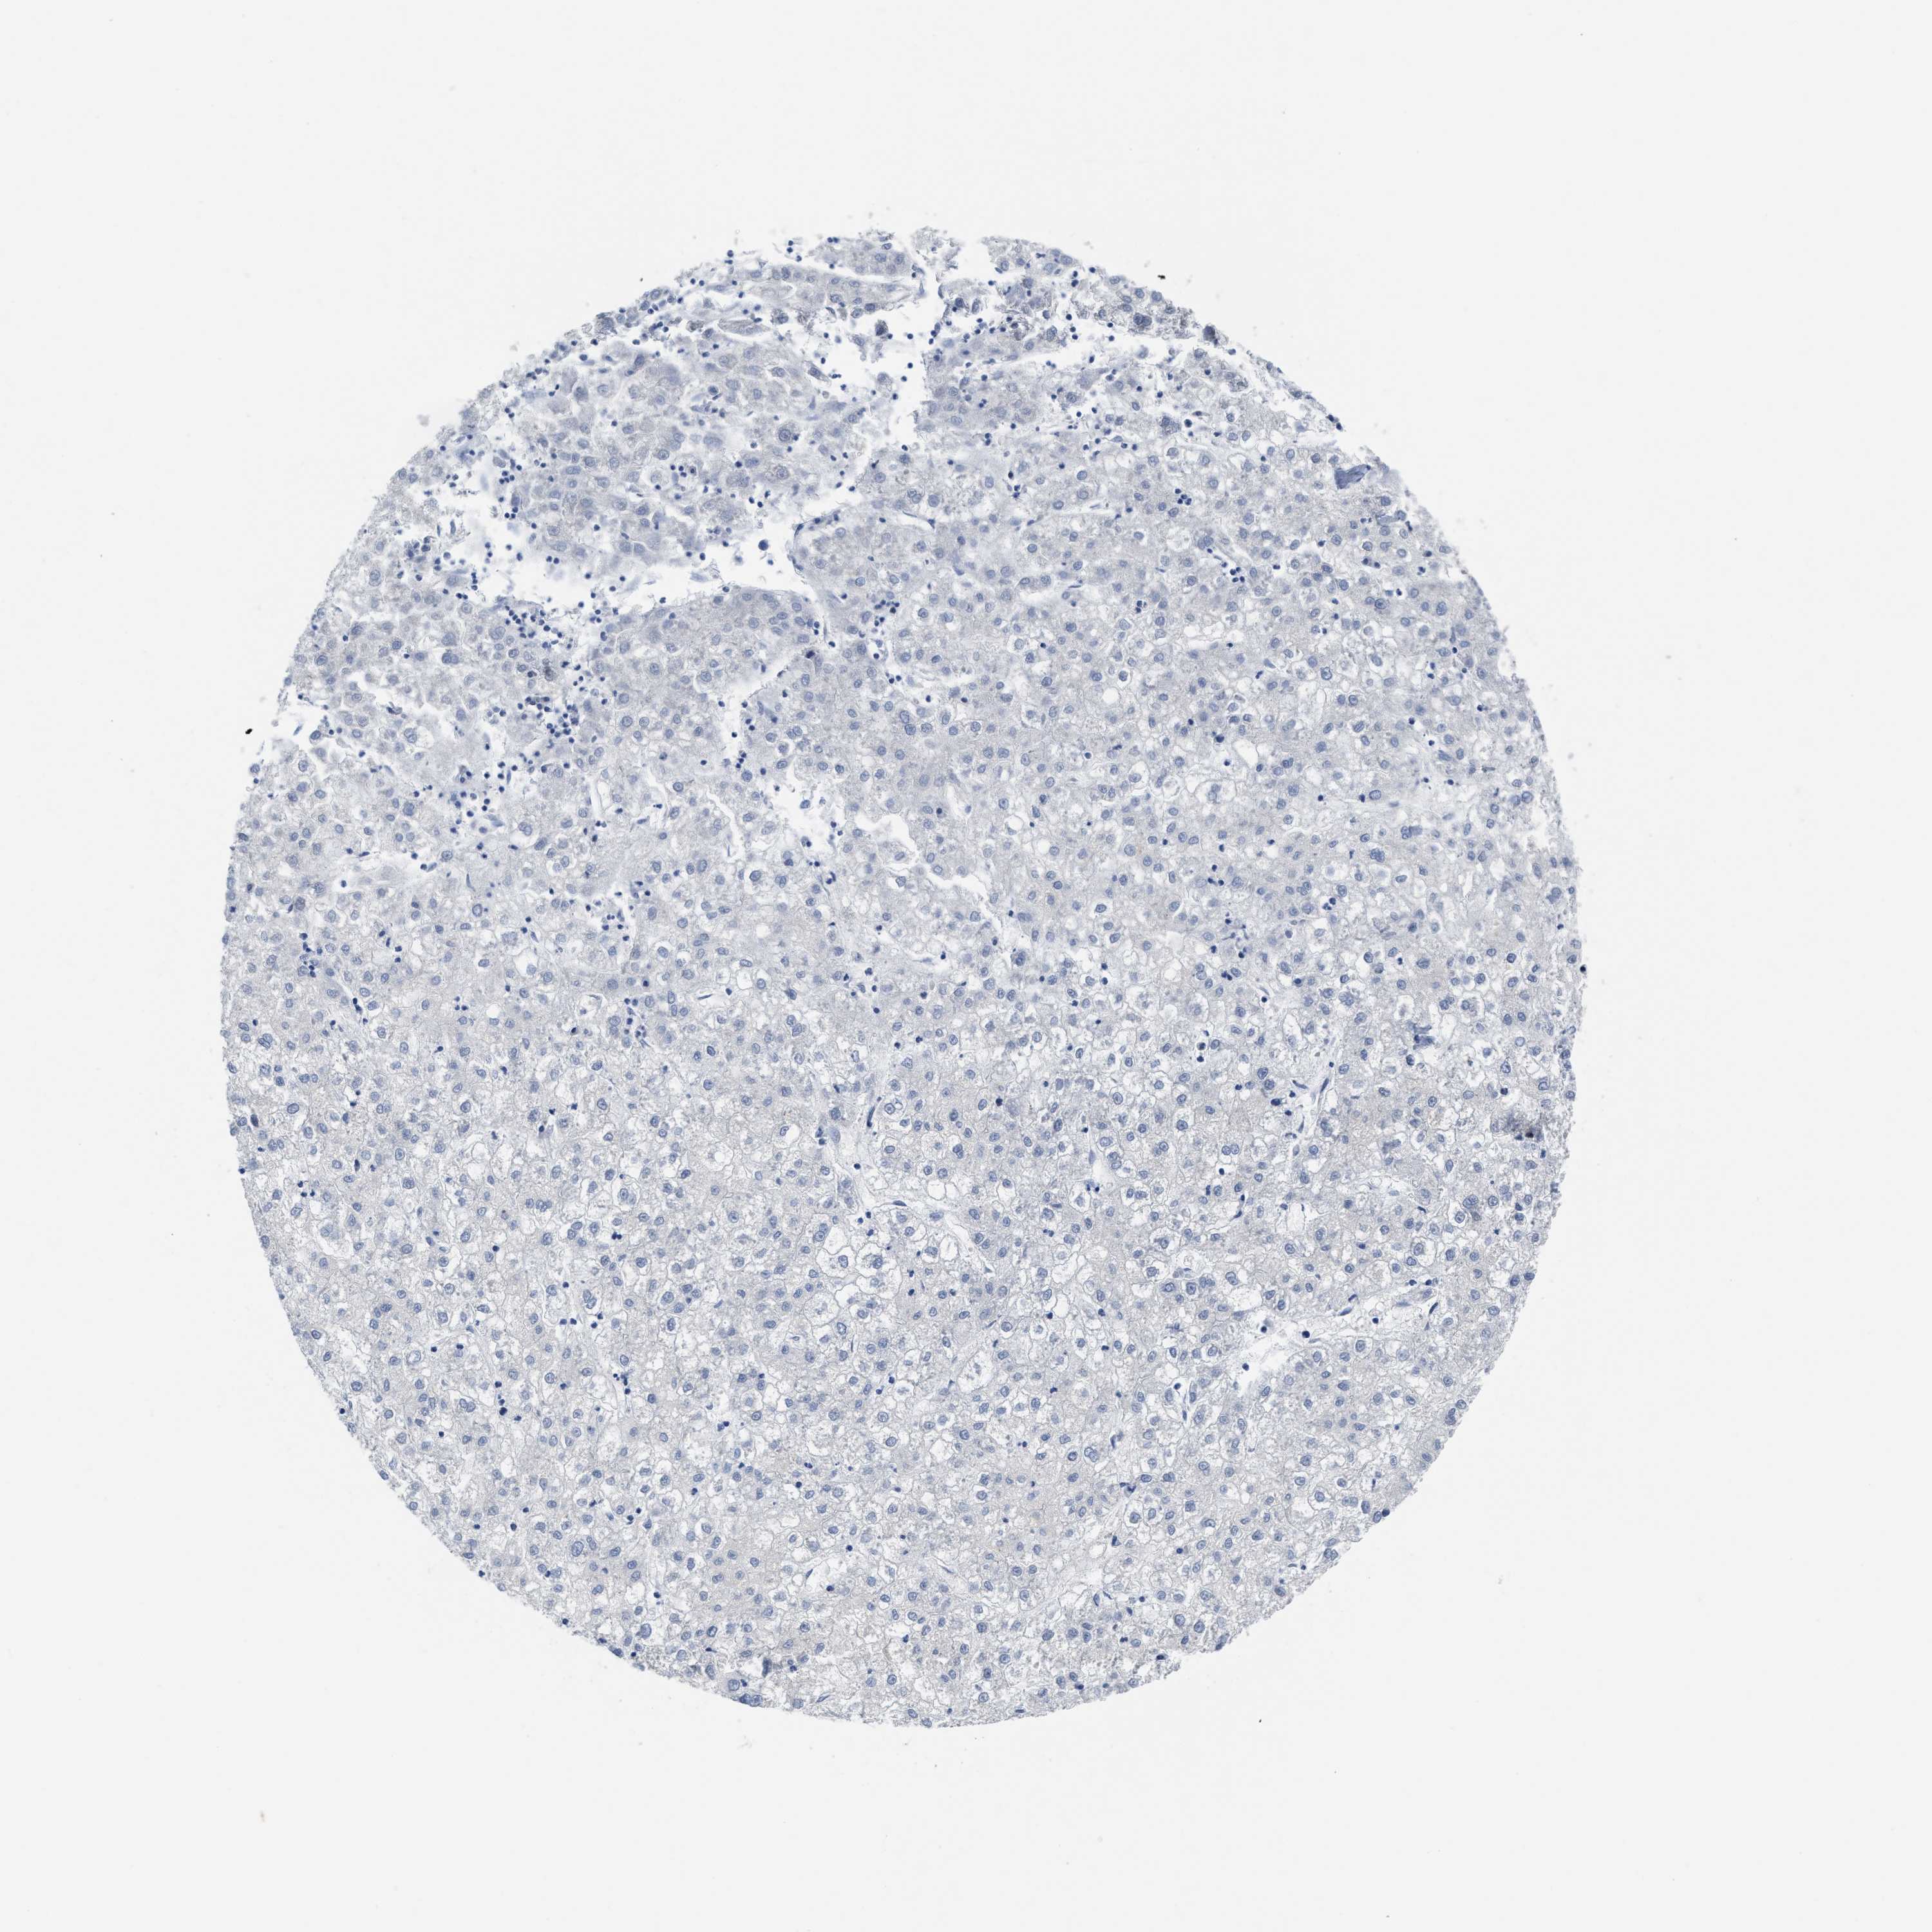

LIVER CANCER - Protein expressioni

A mouse-over function shows sample information and annotation data. Click on an image to view it in a full screen mode. Samples can be filtered based on level of antibody staining by selecting one or several of the following categories: high, medium, low and not detected. The assay and annotation is described here.

Note that samples used for immunohistochemistry by the Human Protein Atlas do not correspond to samples in the TCGA dataset.

Antibody stainingi

Antibody staining in the annotated cell types in the current human tissue is reported as not detected, low, medium, or high, based on conventional immunohistochemistry profiling in selected tissues. This score is based on the combination of the staining intensity and fraction of stained cells.

Each image is clickable and will lead to virtual microscopy that enables deeper exploration of all samples and also displays staining intensity scores, fraction scores and subcellular localization as well as patient and tissue information for each sample.

Antibody HPA001275

Antibody CAB017442

Staining

High

Medium

Low

Not detected

Intensity

Strong

Moderate

Weak

Negative

Quantity

>75%

75%-25%

<25%

None

Location

Nuclear

Cytoplasmic/membranous

Cytoplasmic/membranous,nuclear

Carcinoma, Hepatocellular, NOS

Cholangiocarcinoma